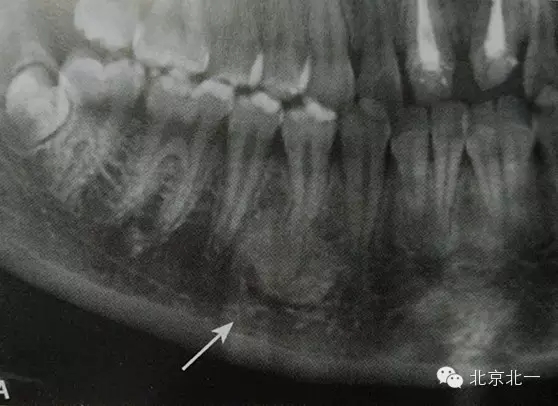

是指根尖周組織受到輕微緩慢持續(xù)性的低毒性因素刺激,而表現(xiàn)出以骨質(zhì)增生為主的防御性反應(yīng)。一般無自覺癥狀,多見于青年人,下頜第一磨牙多見,常有較大齲壞。

【CBCT表現(xiàn)】:發(fā)生致命性骨炎的環(huán)亞暢游牙體病變,其CBCT表現(xiàn)為圍繞根尖的骨質(zhì)密度增高區(qū),骨小梁增多增粗,骨髓腔變窄甚至消失,與正常骨組織分界不明顯。根尖部牙周膜間隙可增寬,根尖無增粗膨大。

根尖片顯示D6深齲,根尖低密度區(qū)周圍骨小梁增粗、增多,骨質(zhì)密度增高,骨髓腔變?。ê谏^)。